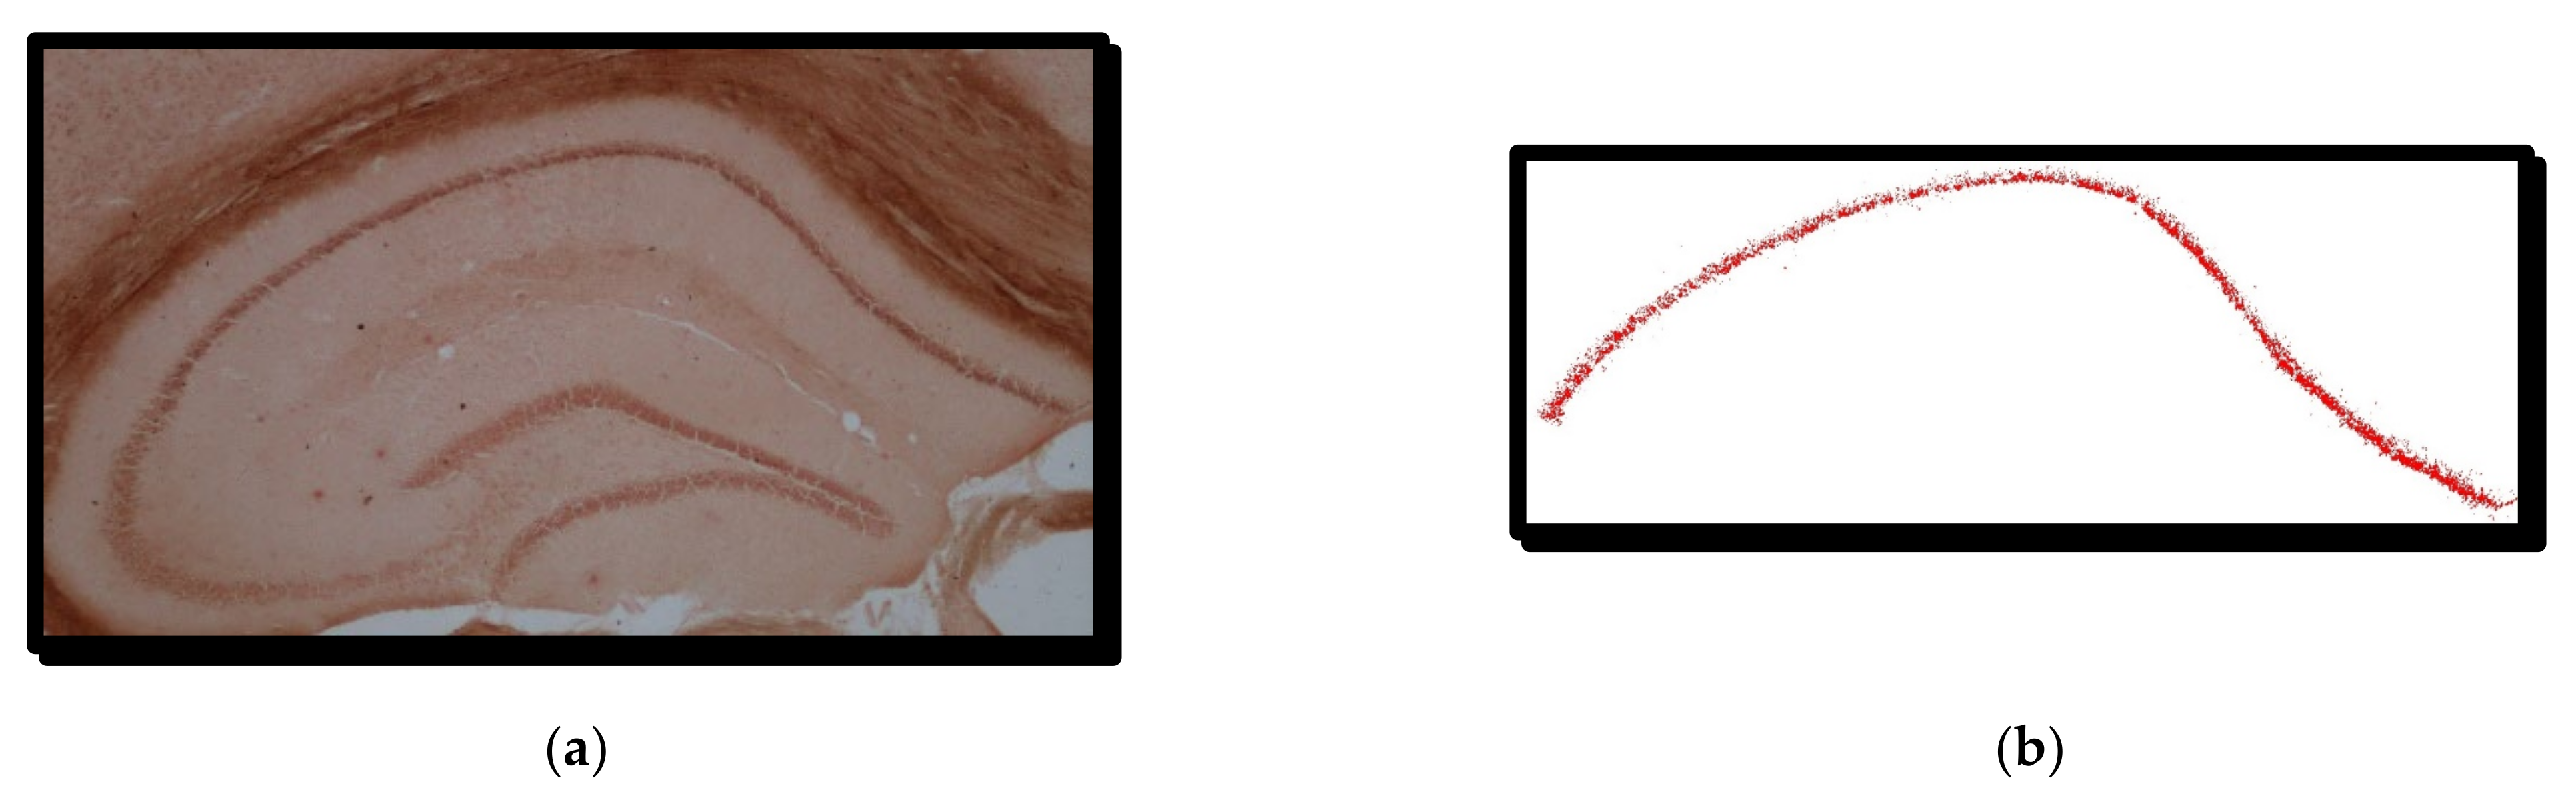

3.4.1. RGB Thresholding Algorithm—The First Method

4.1. RGB Thresholding Algorithm—The First Method